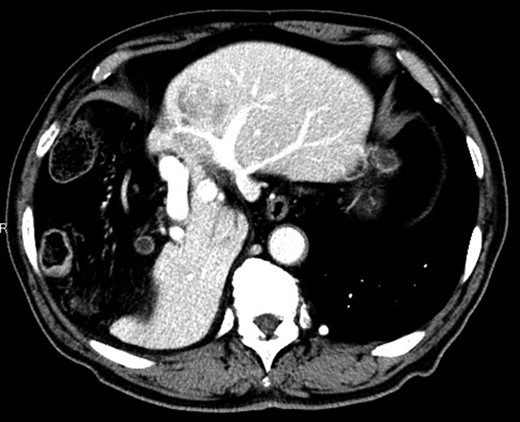

Considering the small remnant right lobe and abnormal ICG15, we planned to perform laparoscopic anatomical S3 segmentectomy. The procedures were performed using a pressure-controlled carbon dioxide pneumoperitoneum, which was maintained below 12 mmHg. Intraoperative findings showed hypoplasia of the right hepatic lobe and hypertrophy of the left hepatic lobe (Fig. 2). Intraoperative ultrasound (IOUS) was performed to confirm the location of the tumor and its relationship to the adjacent structures. The Glissonian pedicle to S3 was isolated with meticulous dissection and was then transected using the SigniaTM Stapling System and Endo GIATM Curved Tip Reload with Tri-StapleTM Technology 30 mm, Vascular Medium (Covidien, USA) (Fig. 3). The ischemic margin of S3 was marked using electrocautery (Fig. 4). Using the crush-clamp method with a harmonic scalpel (Ethicon, USA), the liver parenchyma was transected along the left hepatic vein (Fig. 5). Pringle’s maneuver was performed by clamping the hepatoduodenal ligament using the tourniquet method for 15 min with following a 5-min release period, and a total of fourteen temporary clamps were performed during parenchymal resection. The resected specimens were removed in a retrieval bag through an umbilical port site. The resected specimen showed a 41-mm simple nodular type of HCC and a 5-mm tumor-free resection margin (Fig. 6). Each port was placed as shown in Fig. 7.

The Glissonian pedicle to S3 was transected using the SigniaTM Stapling System.